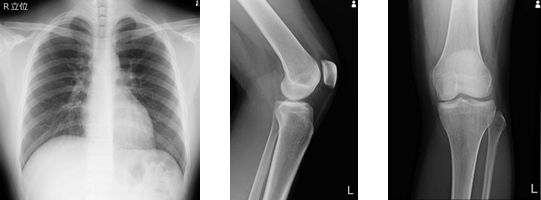

一般撮影検査

一般撮影とは、俗にいうレントゲン撮影のことです。X線を照射して胸やお腹、全身の骨などの透過像を撮影し、胸部(肺や心臓)の異常影、腹部の腸管ガス・結石など病気のおおまかな状態や骨折などを把握出来ます。当院では2018年12月からほぼ全てFPD(フラット・パネル・ディテクタ)システムで撮影を行い被ばくの低減に努めています。

フラット・パネル・ディテクタ(Flat Panel Detector) の略です。X線検出システムであるシンチレータと受光素子が一体化されたパネルで、生体を透過したX線を直接デジタル信号に変換出力することによってレントゲン写真を得 る装置です。従来の装置(CRシステム)と比べて、より高精細 な写真を得ることができるようになりました。

従来の装置システムと比べてX線感度が高いため、線量を減らしても十分な画像が得られることと、

画像処理技術の向上によりX線の照射線量を最大約40~50%低減可能となっています。

従来の装置では、撮影方向を変える度にカセッテと呼ばれる板を入れ変えなければならなかったのですが、FPDでは板を入れ変える必要性がほぼ無くなりました。これにより時間の短縮だけでなく、痛みを伴う部位の撮影時など身体への負担も軽減出来ます。また、直接画像データを出力するので撮影してから画像が見られるまでの時間も短くなったため、1人あたりにかかる撮影時間が全体で約25~30%も短縮されました。